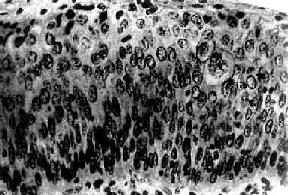

图13-3 子宫颈原位癌

癌变限于上皮层内,细胞核肥大、深染,大小不一,形态不规则,核仁明显,核分裂像易见,且见巨细胞(右侧上方),这种细胞间变累及上皮全层,但基底膜完整,癌细胞未浸润到基底膜下间质